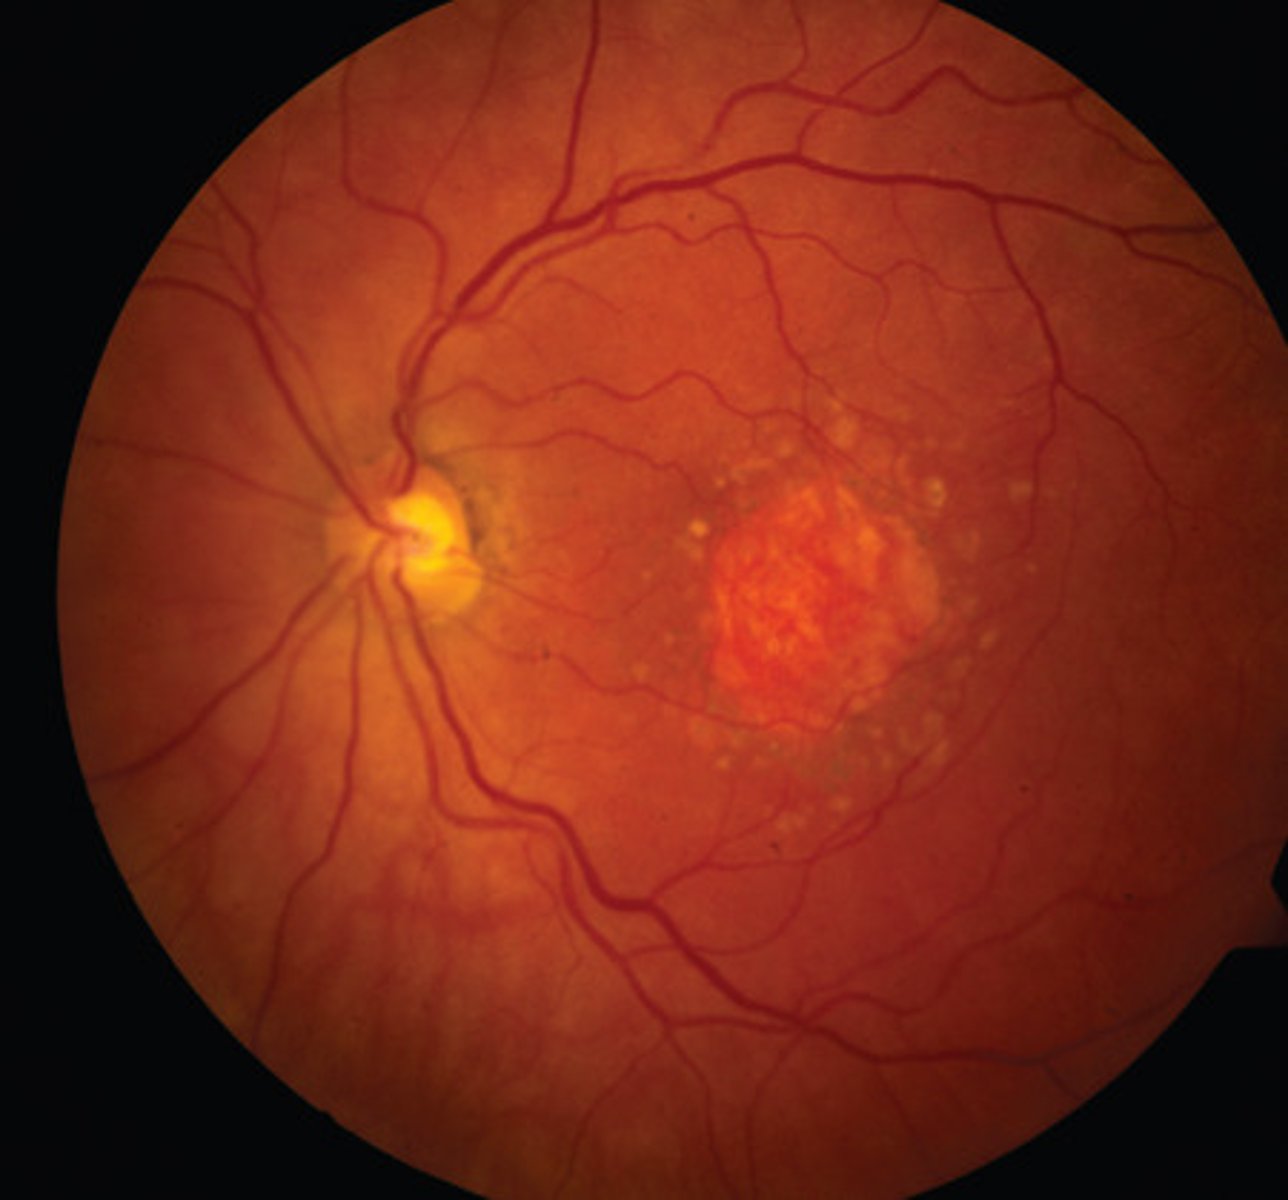

Choroidal naevus : Aetiology

Area of increased choroidal pigmentation

•Benign - low malignancy potential

•Common - prevalence of 2-7%

•Prevalence increases with age

Choroidal naevus signs

Typically small, flat, grey lesions

• May be mottled (drusen and RPE variations)

• Variable shape - round to oval to irregular indistinct margins

• Usually no chorioretinal atrophy, no haloes around the lesion

Choroidal naevus- differential diagnosis

Choroidal melanoma

Choroidal Naevi: Management

Baseline colour photography (or careful drawing)

• OCT and autofluorescence to look for sub-retinal fluid and lipofuscin

• Urgent (within 2 weeks) referral:

• Any one of – thickness > 2mm (or LBD > 7mm), collar stud configuration,

documented growth

• Any two of – thickness > 1.5mm (or LBD > 6mm), orange pigment, serous

detachment, symptoms

• Otherwise routine exam with patient education